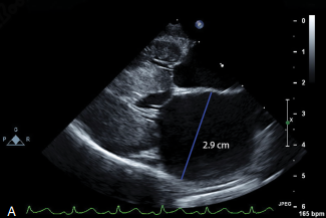

Dày thành thất trái kỳ tâm trương (a) và tâm thu (b)

Dày thành thất trái (LV thickness)

Đối với mèo trường thành với kích thước trung bình thường có thành tự do thất trái và vách liên thất < 5mm, các giá trị > 6mm thường quá dày ở mèo có kích thước bình thường. Khoảng nghi ngờ từ 5-6mm, độ dày thành thất trái thường thay đổi theo cân nặng cơ thể (khoảng 1mm từ 2- 8kg). Vẫn còn nhiều tranh cãi về việc >6mm ở những con mèo kích thước lớn (>10kg).

HCM ở mèo thường xảy ra khu trú, do đó sự bất đồng theo vùng cần phải kiểm tra kỹ lưỡng bằng siêu âm 2D. Siêu âm tim M-mode không được sử dụng để sàng lọc dày thành thất trái khu trú, tuy nhiên có thể sử dụng tại vị trí đã xác định từ trước bằng chức năng siêu âm tim M-mode theo vị trí giải phẫu (Anatomical/Free-positioning M-mode). Tuy nhiên, độ dày thành tim nên được đo trên hình ảnh 2D kỳ tâm trương bao gồm cả bề mặt nội tâm mạc (nguyên tắc leading edge to trailing edge với vách liên thất).